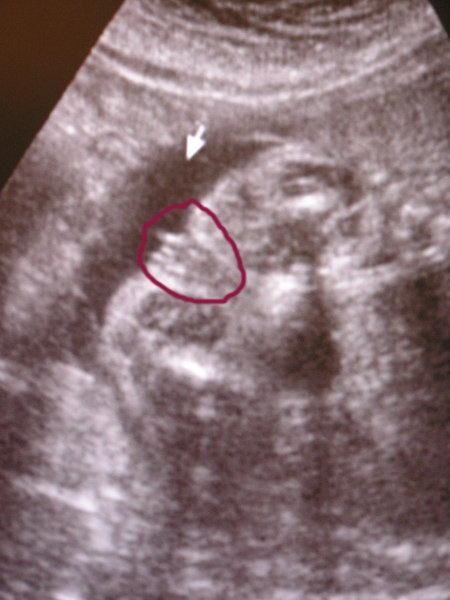

Megjöttünk, az uh-ról, nem tudtam előbb jönni, mert főznöm kellett.

Szóval minden rendben van. Képzeljétek el először oldalt feküdt, utána hanyadt vágta magát, és az egyik kezét a feje alá tette, utána a másik kezével matatott. Aztán a másik kezét is a feje alá tette. Utána meg a fejét felemelte és az egyik kezével az állát fogta a másik meg a feje alatt volt. Annyira jó volt nézni, hogy el sem hiszitek. És annyira érdekes hogy már ilyen picikén ilyeneket csinál. Még a könnyem is kicsordult. Van fénykép is, csa a szkennelt apa lehúzta úgy hogy egyenlőre csak lefotózni tudtam.

Még apa is elérzékenyült.

Méretei: BPD 40 mm

HC 14 cm

OFD 48,6 mm

FL 2,37 cm

AC 11,86 cm

Kb 15-20 cm között van, és 20 g a drágám. Na és KISLÁNY